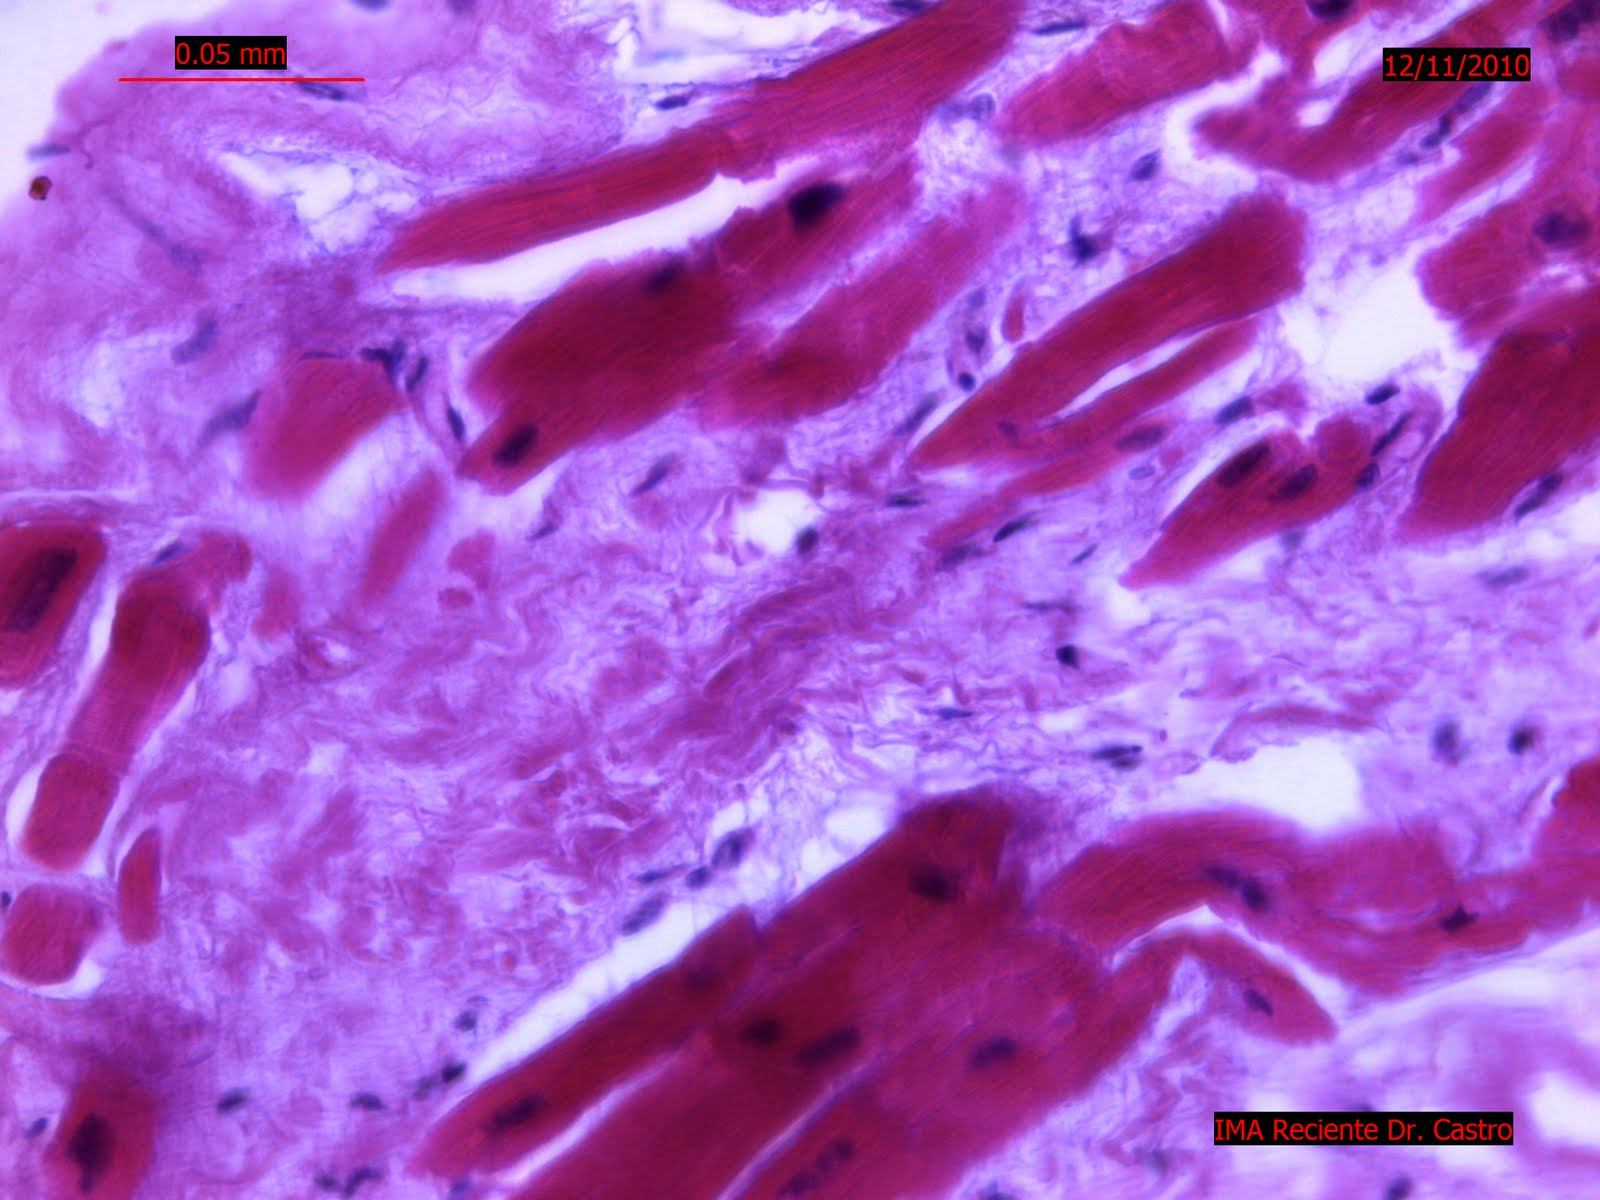

- Los hallazgos histopatologicos encontrados en tejido cardiaco debidos a un vasoespasmo severo de la arteria Carotida ocasiona un infarto masivo como mostramos en la imagen con una clara eosinofilia citiplasmatica del cardiomiocitos, alteraciones arquitecturales citoplasmaticas y hipercromasia nuclear.